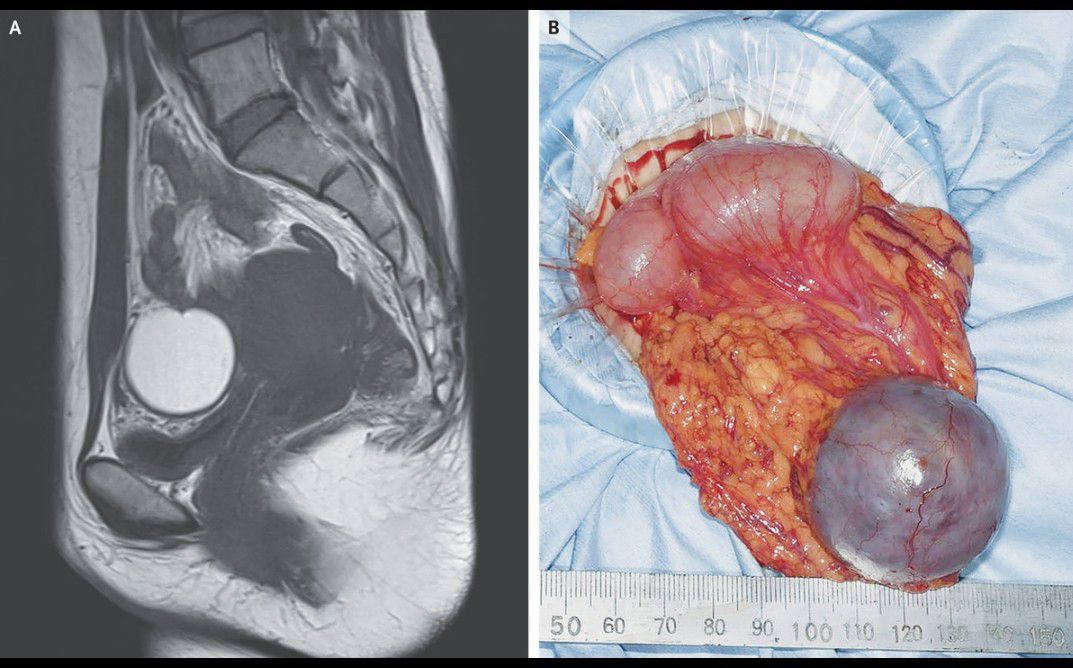

A 37-year-old woman presented to the outpatient gynecology clinic with crampy lower abdominal pain that occurred during menstruation. Her medical history was notable for ovarian endometriosis, which had been treated laparoscopically 5 years earlier. Magnetic resonance imaging revealed a cystic mass, measuring 4.1 cm by 4.1 cm by 4.1 cm, in the lower abdomen that had a high signal intensity on T1-weighted imaging (Panel A). A laparoscopy was performed, and the mass was found to be of omental origin (Panel B; loops of bowel are also visible). The uterus and ovaries appeared normal. Pathological examination of the resected mass showed findings consistent with endometriosis. Endometriosis of the omentum is a form of extrapelvic endometriosis. On follow-up 1 month later, the patient reported no further abdominal pain. She became pregnant 15 months after the laparoscopy.